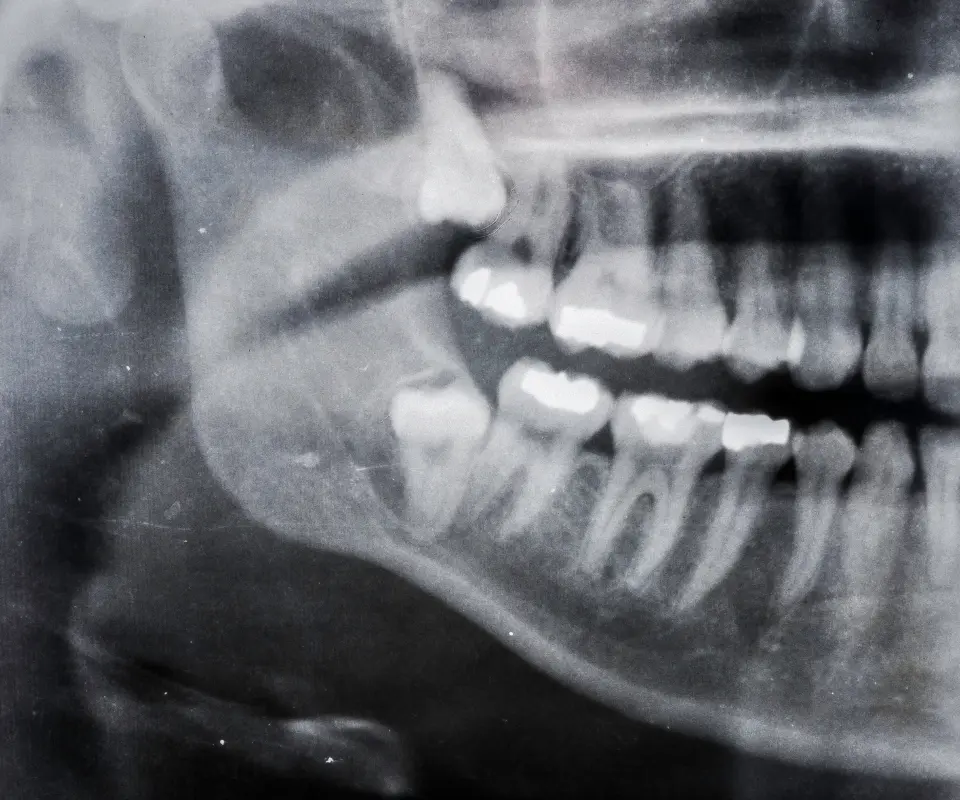

Tooth Abscess

A deep infection inside your tooth can cause severe pain, pus, and swelling in the jaw or face. This is often a dental emergency.

Wisdom Tooth Complications

Swollen jaw after toothache or from impacted wisdom teeth is very common. Conditions like pericoronitis can cause the surrounding gum and jaw area to swell if not treated in time.

What is a dental abscess and how does it cause jaw swelling?

A dental abscess is a pocket of pus caused by a bacterial infection. It typically results from tooth decay, gum infections, or trauma. As the infection spreads, it can cause severe pain and visible jaw swelling. This condition needs urgent dental treatment to avoid further complications.